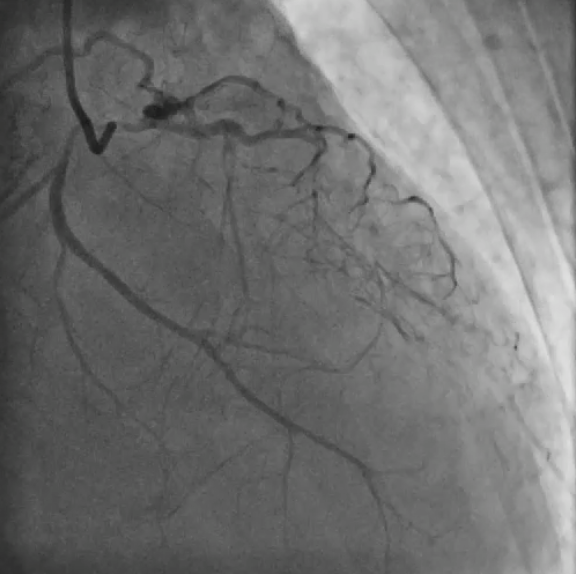

Upon removal of the workhorse wire from distal LAD, an unforeseen nightmare started. The wire tip entangled with the distal stent edge. Turnpike microcatheter was used to retrieve the stuck wire. Unfortunately, upon pullback, the wire fractured and only its proximal part was retrieved. The distal part remain stuck in the distal stent edge and uncoiled with filaments extending from stent edge into aorta. PingPong guiding was immediately set up. ClearStent showed distal stent edge deformity which rendered passage of any device including 1.0mm balloon impossible. In order to modify the obstructing stent struts at distal edge, it was decided to use rotablation. Direct wiring across the deformed distal stent edge with rota wire was successful. Pecking motion of rotablation was performed with the aim to clear the obstructing scaffolds. After 25 runs at high speed with 1.5bur, the deformed distal stent was successfully crossed. The trapped wire tip was unexpectedly released and fell into the septal branch. The fractured filaments were assessed with IVUS and ClearStent. Subsequently, the filaments were all retrieved with 2 twisting wires. IVUS confirmed complete clearance of any filament. The LM-LAD stent was again post dilated and optimized. Final angiogram and follow up restudy 4months later both showed satisfactory result with patent stents.